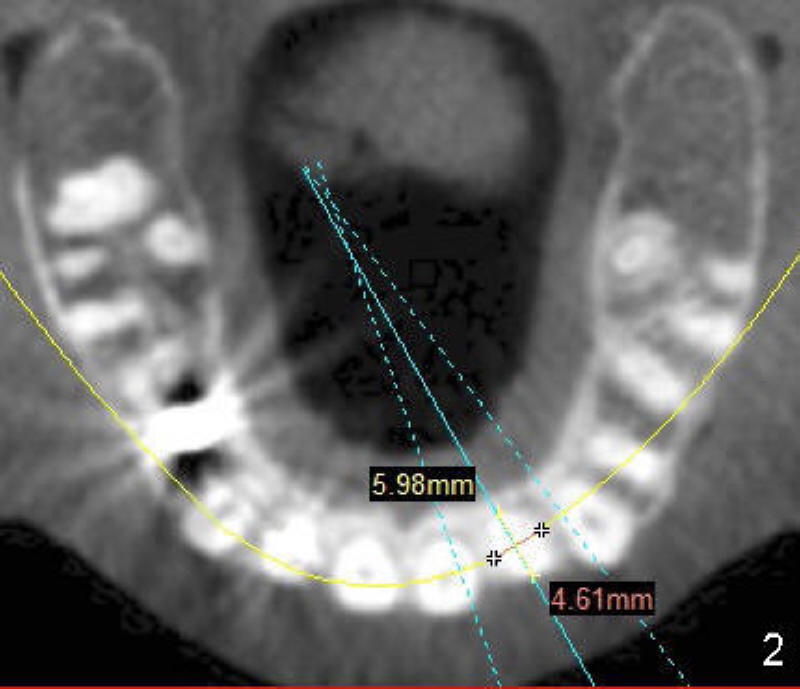

Which of Tatum tapered implants is the most appropriate, 4x17 mm (Fig.4), 4.5x14 (Fig.5) or 5x11 (Fig.6)?

I took a look at the case.  I think that the 4.0 or 4.5 diameter implant is more appropriate.   The 17 length is ideal .  I suggest the smaller diameter implant due to fact that we are replacing a lateral.  I would graft the superior threads with bone allograft.   Bernee Dunson